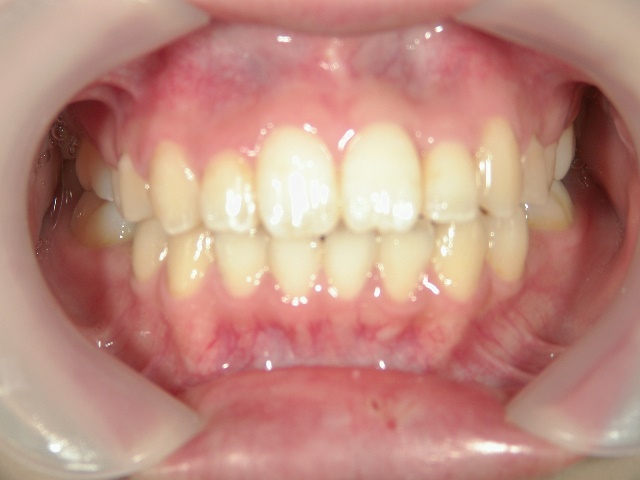

矯正歯科 治療後矯正歯科 プチワイヤー矯正 治療後矯正歯科(プチワイヤー矯正)治療後

矯正歯科 治療後

no.8_8495_治療後_左.jpgno.8_8495_治療後_正面.jpgno.8_8495_治療後_右.jpg